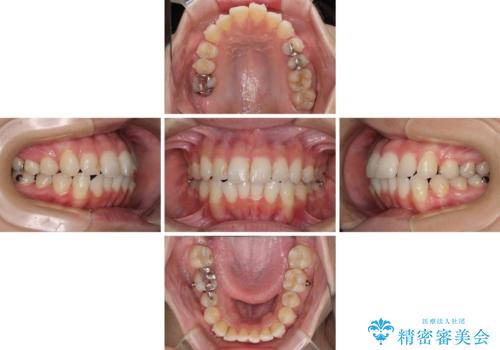

【モニター】前歯のデコボコをインビザラインできれいに整える

- 前歯のデコボコを気にして来院された患者様です。

主に下顎歯列全体の後方移動とIPR(歯と歯の間を削る)によってデコボコが解消するように設計し、インビザラインにより治療を行うこととしました。

舌突出癖がある方ですと、叢生が解消すると同時に前方に拡大されてしまいますが、ゴムかけをしっかりと行ってくださったこともあり、スッキリとした仕上がりとなりました。